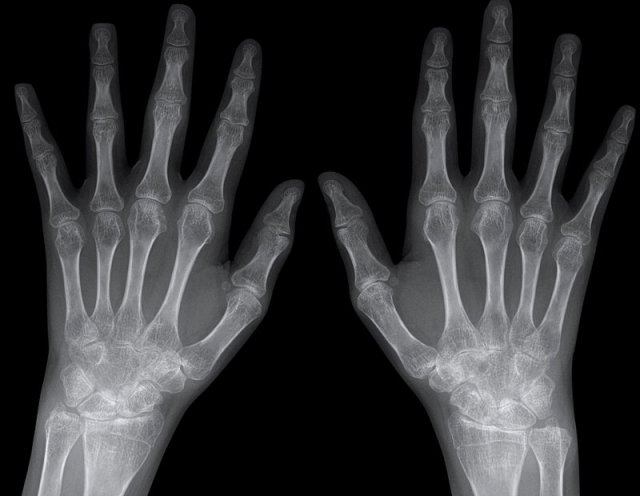

Typical marginal erosions and joint space narrowing of MCP 3-5.

Also note the uniform joint space narrowing of the MCP joints.

The PIP-joints only show minimal joint space narrowing.

End stage Rheumatoid arthritis. End stage Rheumatoid arthritis.

This is a case with end stage rheumatoid arthritis with severe erosive changes and ligamentous ruptures causing dislocation of the MCP joints.

Scapholunate dissociation (white arrow) is a common finding due to diffuse carpal inflammation. Both the dissociation and inflammation can cause joint space narrowing in the radiocarpal joint.

Notice also the erosion in the distal ulna with surrounding soft tissue swelling (blue arrow).